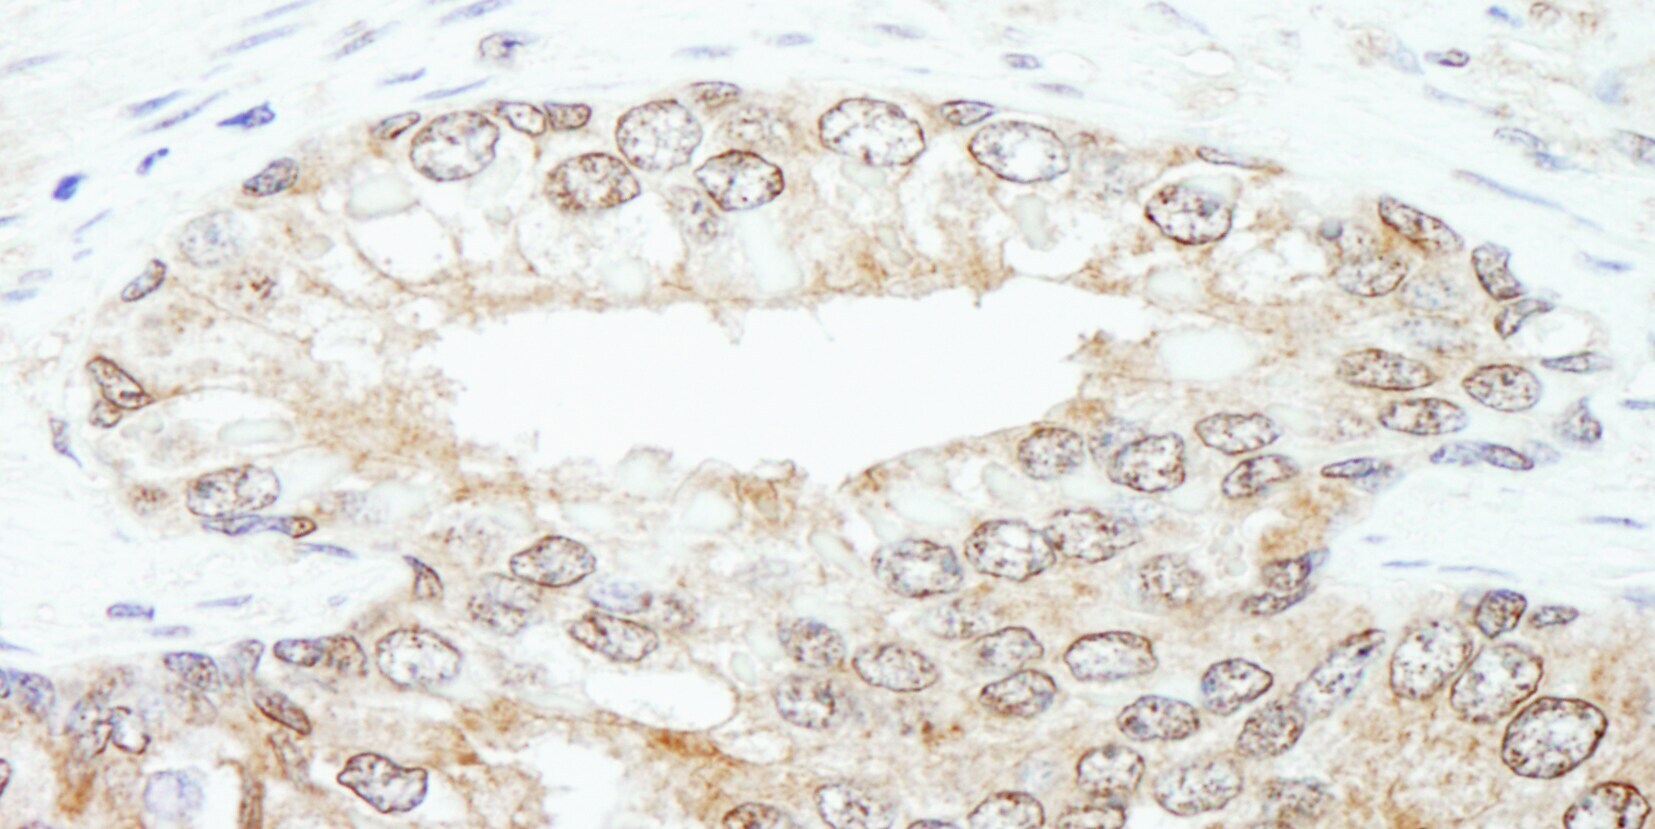

Supportive validation

- Submitted by

- Invitrogen Antibodies (provider)

- Main image

- Experimental details

- Detection of human KPNA3 by immunohistochemistry. Sample: FFPE section of human prostate carcinoma. Antibody: Affinity purified rabbit anti-KPNA3 (Cat. No. A301-626A Lot1) used at a dilution of 1:200 (1µg/ml). Detection: DAB.